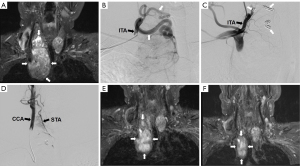

Post-TAE, controlled angiography of the common carotid and the thyrocervical trunk were performed for confirmation of occlusion of the thyroid feeding arteries and obliteration of the thyroid tumor stains. Finally, hemostasis of the radial arterial puncture wound was performed with a rigid TR band (Terumo Interventional, Somerset, NJ, USA) for a duration of two hours (10). Patients were ambulated and discharged as their medical condition permitted on the same day after 1- to 2-hour observation. Images from the representative case are displayed in Figure 1.

Using Simon II catheter, unilateral digital subtraction angiography (DSA) of common carotid artery and thyrocervical trunk (or proximal subclavian artery) were performed to identify the thyroid nodular feeding arteries. Under fluoroscopic road map or overlay controlled, a Synchro-14 microwire and an Excelsior 1018 microcatheter (Stryker, Kalamazoo, MI, USA) were advanced to the feeding arteries. Embosphere microspheres (300–500 or 500–700 µm) (Merit Medical, South Jordan, UT, USA) mixed with iodinated contrast media (1-to-1) was gently injected with a 3-mL syringe by pulsing motion in free flow fashion until stagnation. The proximal parts of the feeding arteries were also occluded by pushable coils (Cook) at the end of the TRA TAE procedure.